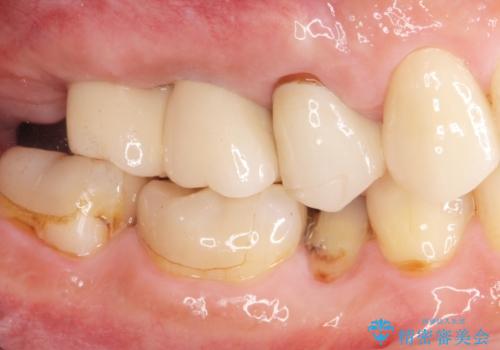

欠損した奥歯 インプラント補綴

天然の歯のようにしっかりと噛むことができるようになり、またしっかりと食事を楽しんでいただけるようになりました。

より清掃性の高い、チタン製カスタムアバットメント、審美製・強度に優れるジルコニアインプラントを用いたインプラント治療を計画します。

- 88万円(インプラント×2・チタンカスタムアバットメント×2・ジルコニアクラウン×2・仮歯×2)費用は治療当時の料金となります